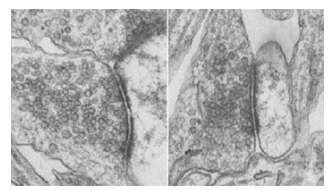

How the neuron releases neurotransmitters has been the focus of considerable research. Scientists discovered neurotransmitters are stored in small, bubble-like compartments called vesicles. Each vesicle tends to hold a single kind of neurotransmitter — say, dopamine, which is associated with memory and other cognitive skills, or serotonin, which helps regulate mood.

The vesicles travel like tiny ferryboats to the end of the neuron, where they dock, waiting to be released. When it is time for the neuron to release neurotransmitters, the vesicles fuse with the membrane of the neuron and dump their contents into the synapse gap. The delicate fusion process — described as the merging of two soap bubbles into one — is highly complex and involves the work of many different and specialized molecules within the neuron. After neurotransmitter release, the neuron recycles the empty vesicles, refilling and reusing them several more times before they need to be replaced.